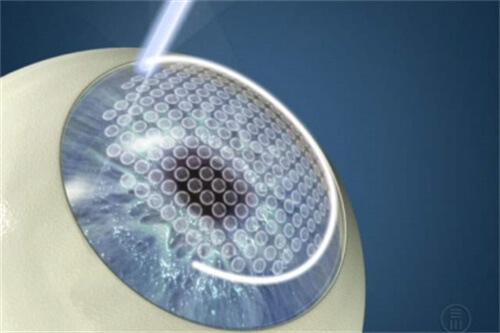

三焦点晶体:相比传统单焦点,可同时优化远、中、近视力,术后不用戴老花镜。

个性化方案:根据患者角膜状况、用眼习惯定制手术,比如喜欢看书或开车的老人,医生会调整晶体参数优化视觉结果。